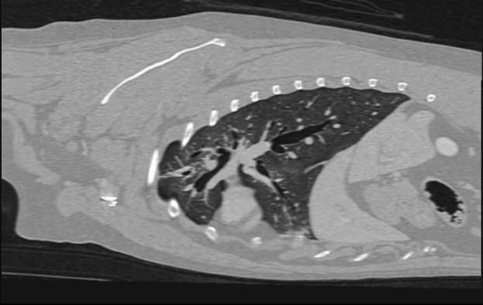

Thoracale regio - borstwand, hart, longen en mediastinum.

Slokdarm vreemd voorwerp, tumor, mediastinum tumor, lymphoma, thymoma

bronchitis, pneumonie, fibrose, longtorsie, oedeem, neoplasie,

pleurale tumoren, diafragma hernia.